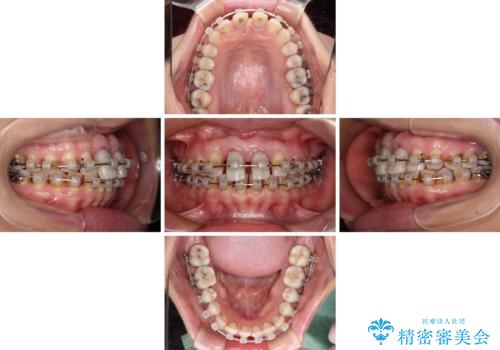

- 矯正装置

- クリアブラケット

- 治療期間

- 2年6ヶ月

- 治療回数

- 30回以上